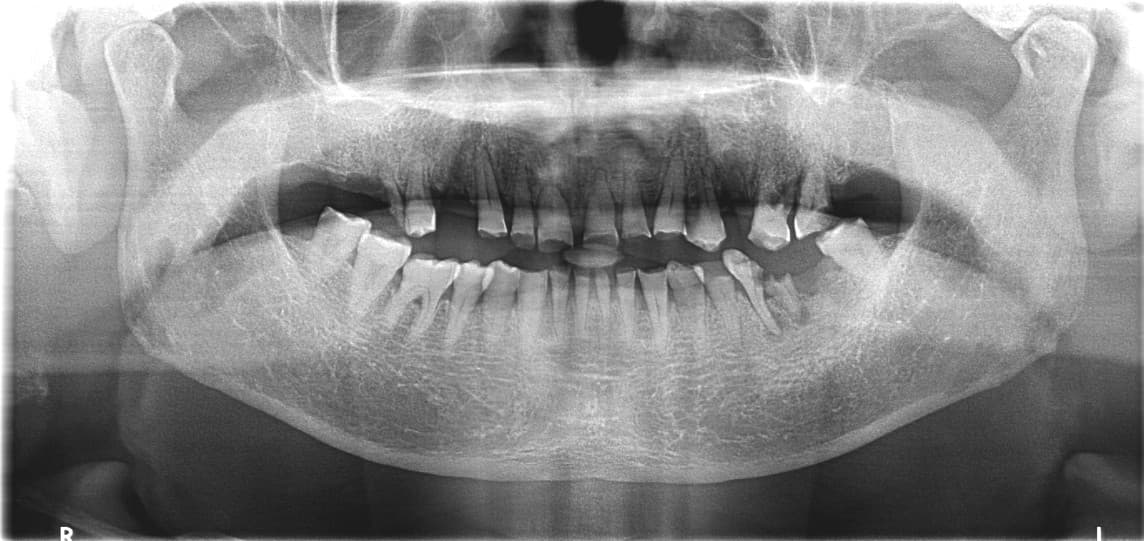

COST-EFFECTIVE TREATMENT

Protez mutaxassisi tomonidan

shaxsiy og'iz bo'shlig'ini tiklash

Implant, toj, ko'prik va boshqalar

Bemor holatiga mos eng maqbul davolash kombinatsiyasi bilan

maqbul narxda eng yaxshi natija

Barcha tishlarni implant qilish shart emas

Toj, ko'prik, qisman protezni to'g'ri kombinatsiyalash bilan xarajatni minimallashtirish

Bemor holatiga mos optimal davolash rejasi

Kang●● · 50 yoshdan oshgan erkak

Implant + Toj + Ko'prik kombinatsiyasi

After ✨

Song●● · 60 yoshdan oshgan ayol

Shaxsiy protez kombinatsiyasi davolash

Jo●● · 50 yoshdan oshgan ayol

Tejamkor shaxsiy davolash